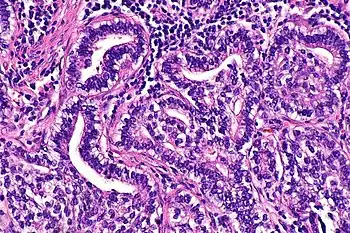

| Micrograph showing fetal adenocarcinoma. H&E stain. | |

Fetal adenocarcinoma (FA) of the lung is a rare subtype of pulmonary adenocarcinoma that exhibits tissue architecture and cell characteristics that resemble fetal lung tissue upon microscopic examination. It is currently considered a variant of solid adenocarcinoma with mucin production.[1]

FA is an epithelial tumor whose cells and architecture resemble that of fetal lung tissues in the pseudoglandular stage of development (which occurs at about 10–16 weeks gestation in the human),[6] with complex glandular structures and morules with cell nuclei that appear clear due to the accumulation of biotin.[15]